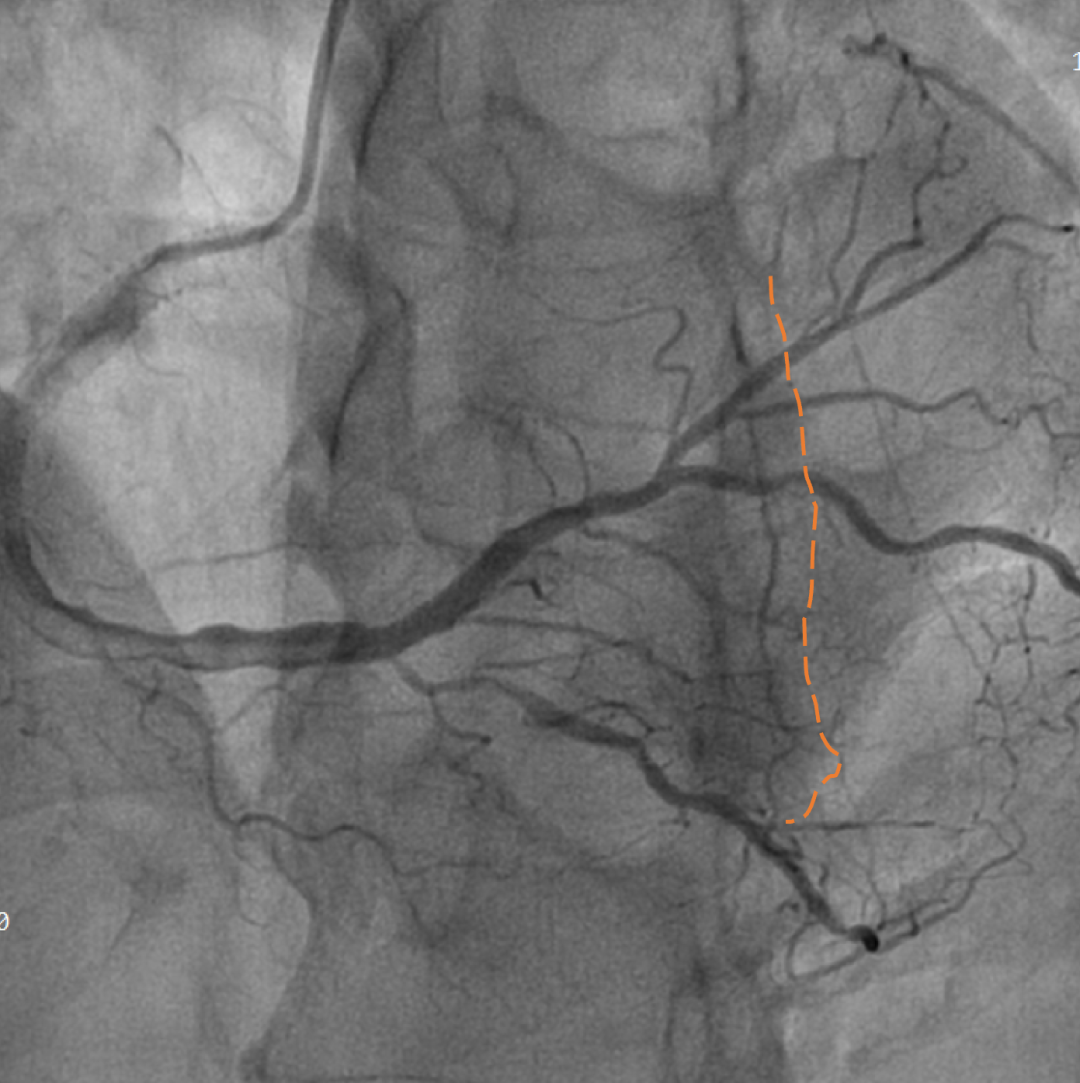

手术影像

左冠优势,LM、LCX未见狭窄,TIMI3级;LAD近段CTO,TIMI0级

RCA细小,近中段狭窄40%-50%,TIMI3级;远端可见LAD侧枝血流

策略讨论:近端纤维帽不清晰,LAD中段显影可见,闭塞段长度>20mm。间隔支逆供条件尚可。CTA提示LAD多发钙化。尝试正向开通,优选亲水性滑导丝,若失败,及时调整逆向策略。